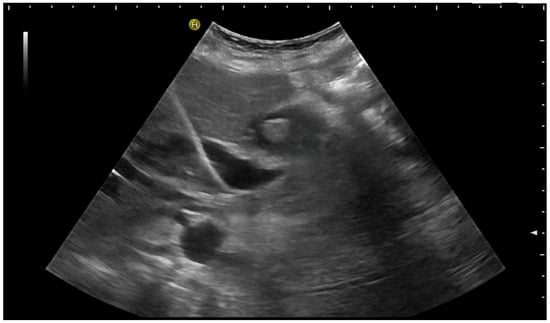

Then, a thin 0.018” guide wire is placed through the needle into the bile duct. Subsequently, a plastic 5F catheter is inserted over the wire. Thin metal guide wires are clearly visible on the US (Figure 8), but usually, the procedure is continued under fluoroscopic guidance to advance the wire across the stricture into the duodenum.

The 0.018” guide wire is very well-depicted by US. The 5F plastic catheter will subsequently be placed; however, there is poor sonographic visibility.

Subsequently, exchanging to larger and more stable 0.035” guide wires allows stepwise bouginage of the tract and the placement of drainage [3,14,41,42]. Ideally, drainage should be placed with side holes above and below the stenosis and the tip in the duodenum for combined extern–intern drainage. If the placement across the stricture into the duodenum fails, external drainage can be placed.

If external drainage is initially planned, it can be placed under US guidance alone; fluoroscopy and cholangiography are not necessary. External drainage has a higher risk of dislocation; therefore, a pigtail catheter should be chosen to reduce this risk. A thread lock that prevents the uncoiling of the pigtail may be helpful, too.